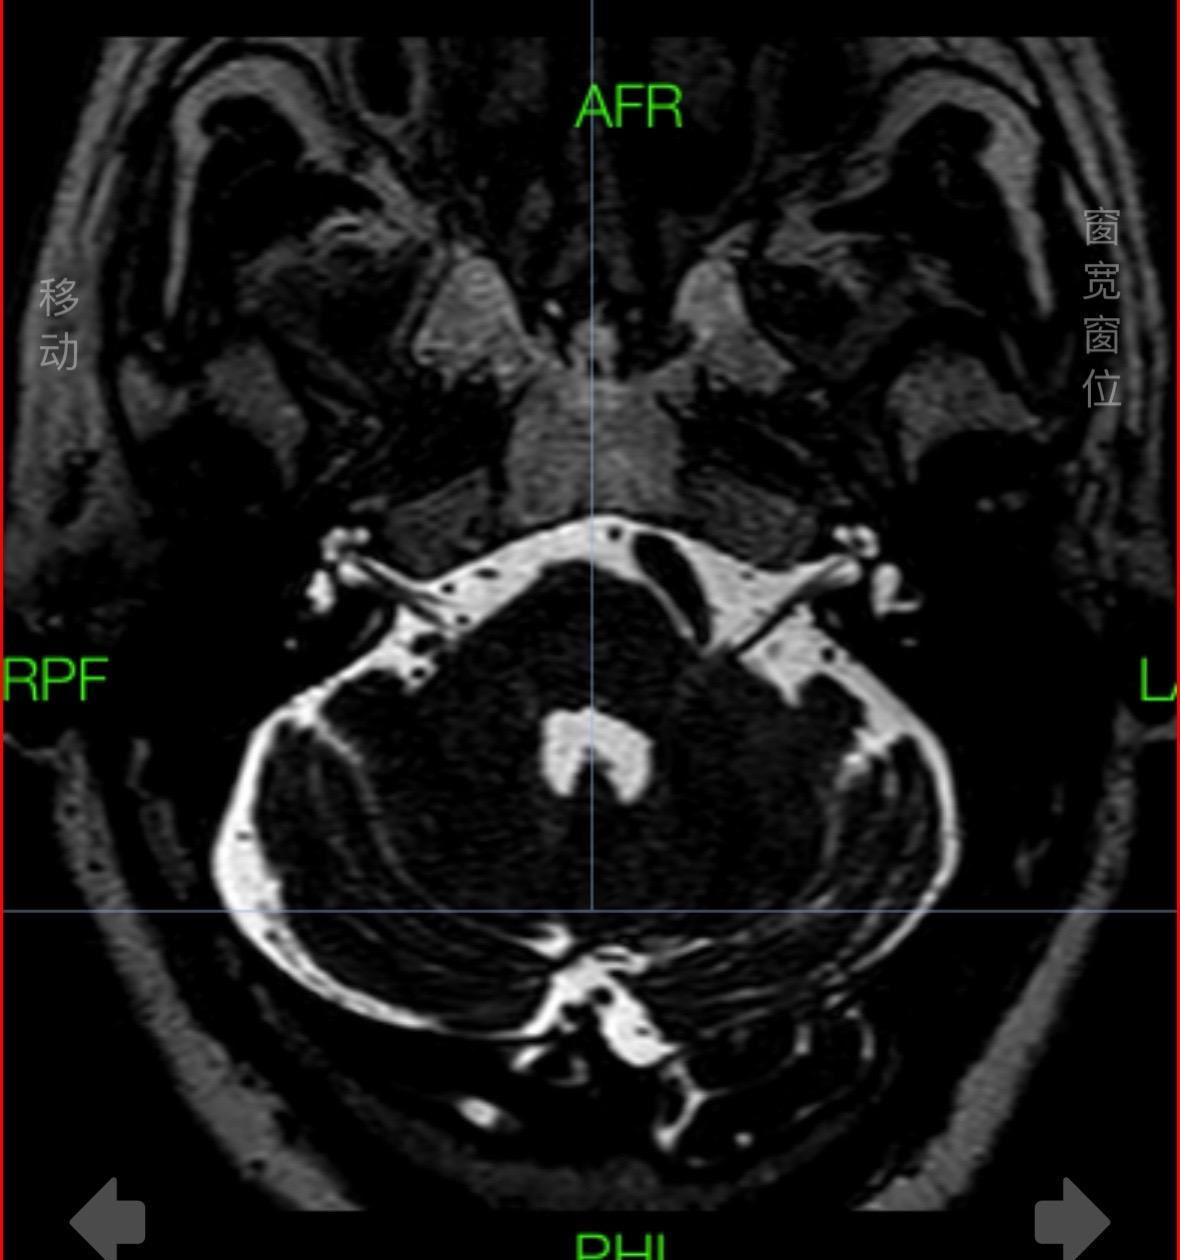

今日三台手术。手术室日常 1.椎动脉压迫导致的面肌痉挛,血管如蟒蛇般缠绕,减压术后脸皮不再跳;2.手指麻木、疼痛、肌肉萎缩,是周围神经的标志性特征,手术治疗后缓解;3.臂丛神经断裂和损伤,5-7大部分断裂,只能一期松解,二期利用自体神经行颈7神经移植